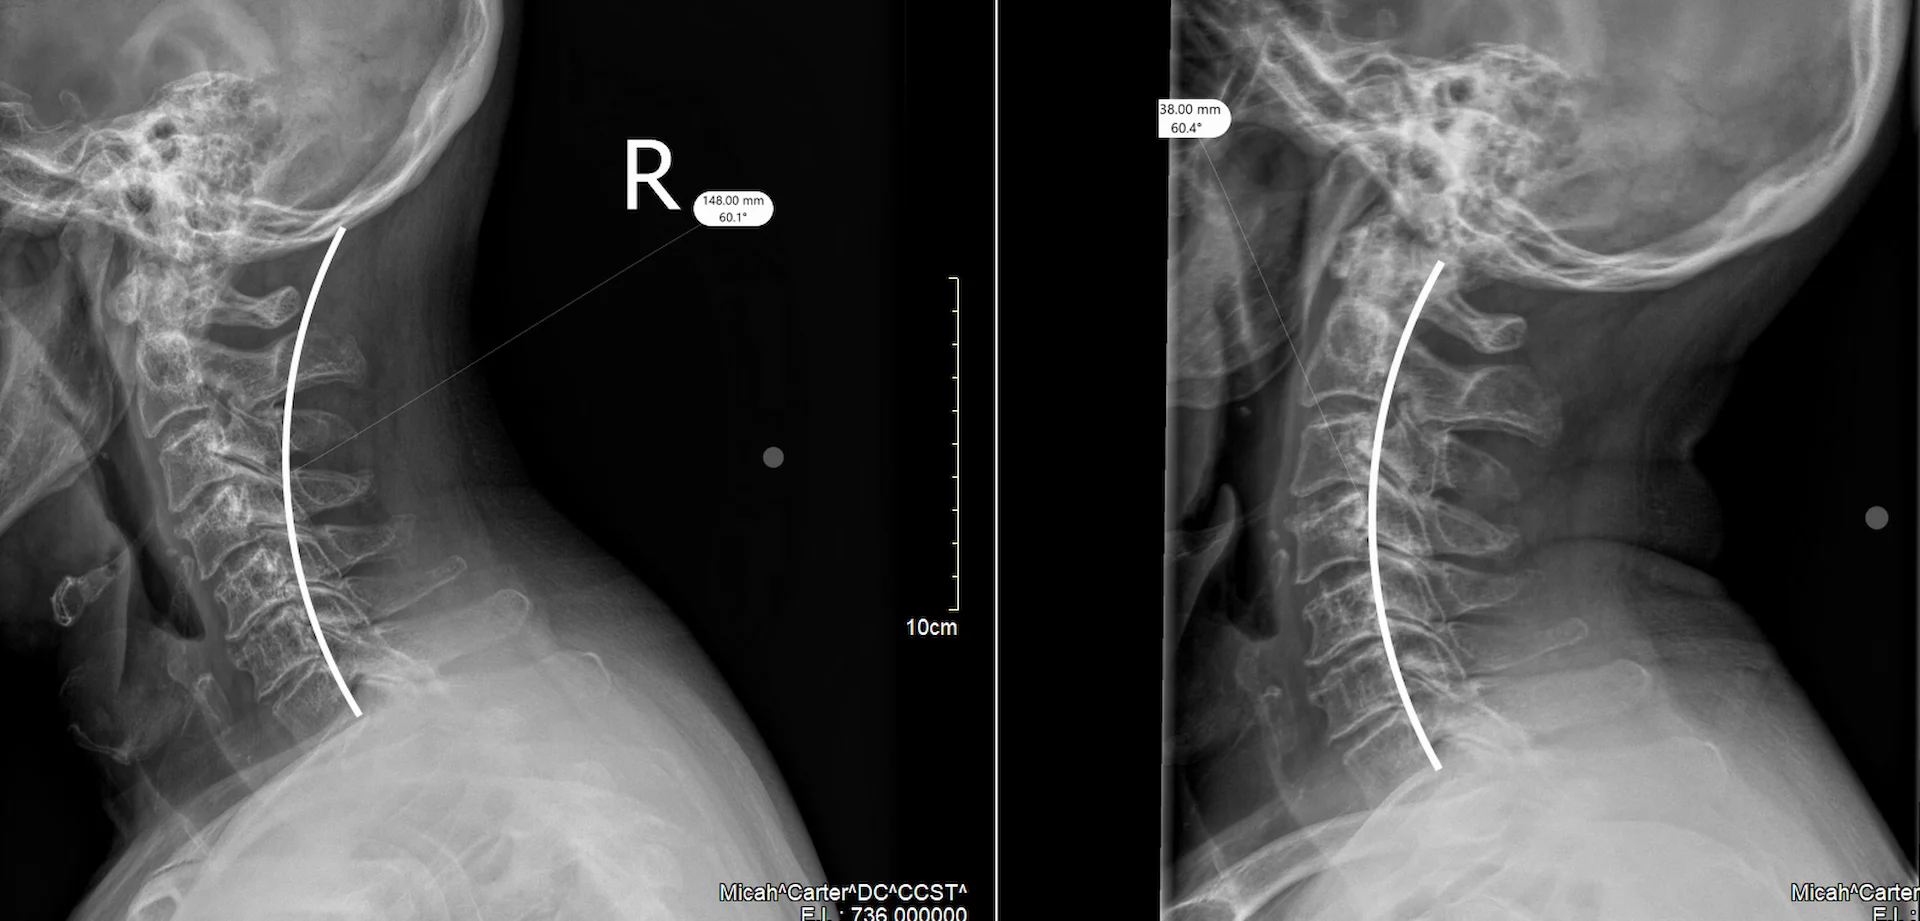

Neck-curvature-before-and-after-xrays-chiropractic